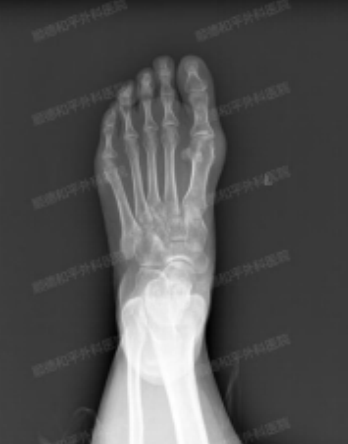

42岁的韦女士,就一直深受先天性拇外翻的困扰,特别是左足,随着年龄的增长,情况逐年恶化。去年还曾前往当地医院接受了手术矫正治疗,但效果并不长久,近期发现拇外翻悄然复发了。

我院骨科四区(足踝外科)程忠勇主任耐心倾听了韦女士的病史,一下就明白了为何她在初次手术治疗后效果并不长久,因为外院医生采用的是落后的拇外翻第一代MIS技术,不使用内固定,且仅用纱布外固定,后续回归正常的生活工作中极易复发。

并细心地介绍了我院目前对拇外翻治疗,已更新到了最新的术式——第四代微创拇外翻手术(MICA),手术优势:包括旋前纠正、固定强度和减少复发的步骤,同时结合主动的三维复位操作,以矫正所有畸形平面,用两个螺钉进行刚性稳定的双皮质固定,以允许早期的负重和康复。

手术耗时也很短,仅1个多小时,只在左足患处各留下三个0.3cm的小切口,术中出血量少,术后恢复速度也更快。严格按照术前设计精准矫形,整个手术过程严谨、精细且高效。细致的诊查结合摄片综合判定,韦女士的情况可以通过该术式进行治疗。

5月7日,安排好个人时间的韦女士,再次返回到我院接受第四代微创拇外翻手术(MICA)治疗。在程忠勇主任及其团队的精心操作下,手术进展十分顺利。手术第二天,韦女士就能穿前足减压鞋逐步下床活动,患者恢复状况良好,术后三天成功出院。

第四代微创踇外翻矫正手术技术是一种安全有效的处理踇外翻畸形的方法,在广泛的畸形矫正中取得了显著的临床和影像结果的改善。相信韦女士出院后,多加注意,很快就能康复并正常行走,穿鞋也不再是困扰,并确保后续不再复发。